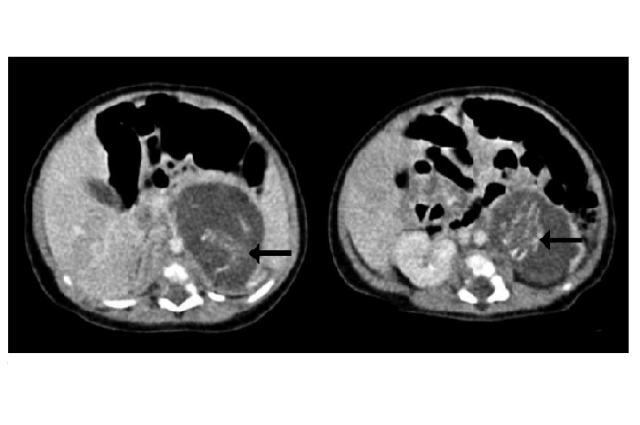

È il caso di una bambina cinese nata presso il Queen Elizabeth Hospital di Hong Kong nel novembre 2010. Un’ecografia, mentre era ancora nel grembo della madre, ha permesso di rilevare una massa abnorme all’interno del suo addome, che i medici sospettavano essere un tumore o un’emorragia.

Un esame più approfondito ha permesso di rilevare la presenza di due lunghe ossa e di una colonna vertebrale. I medici hanno quindi deciso di operare la neonata dopo soli 14 giorni dalla nascita e l’estrazione delle due masse ha reso possibile scoprire che si trattava di due feti, uniti da un cordone ombelicale.

L’esame delle masse asportate ha dunque rivelato due feti, dotati entrambi di cordone ombelicale, spina dorsale e piccoli organi. Pur essendo di diverse dimensioni, il livello di sviluppo era identico. Entrambi possedevano quattro arti, spine segmentate, gabbie toraciche ben sviluppate, tessuto cerebrale primitivo, intestini, un ano e pesavano 14 e 9 grammi. Il fenomeno è conosciuto come fetus in fetu.